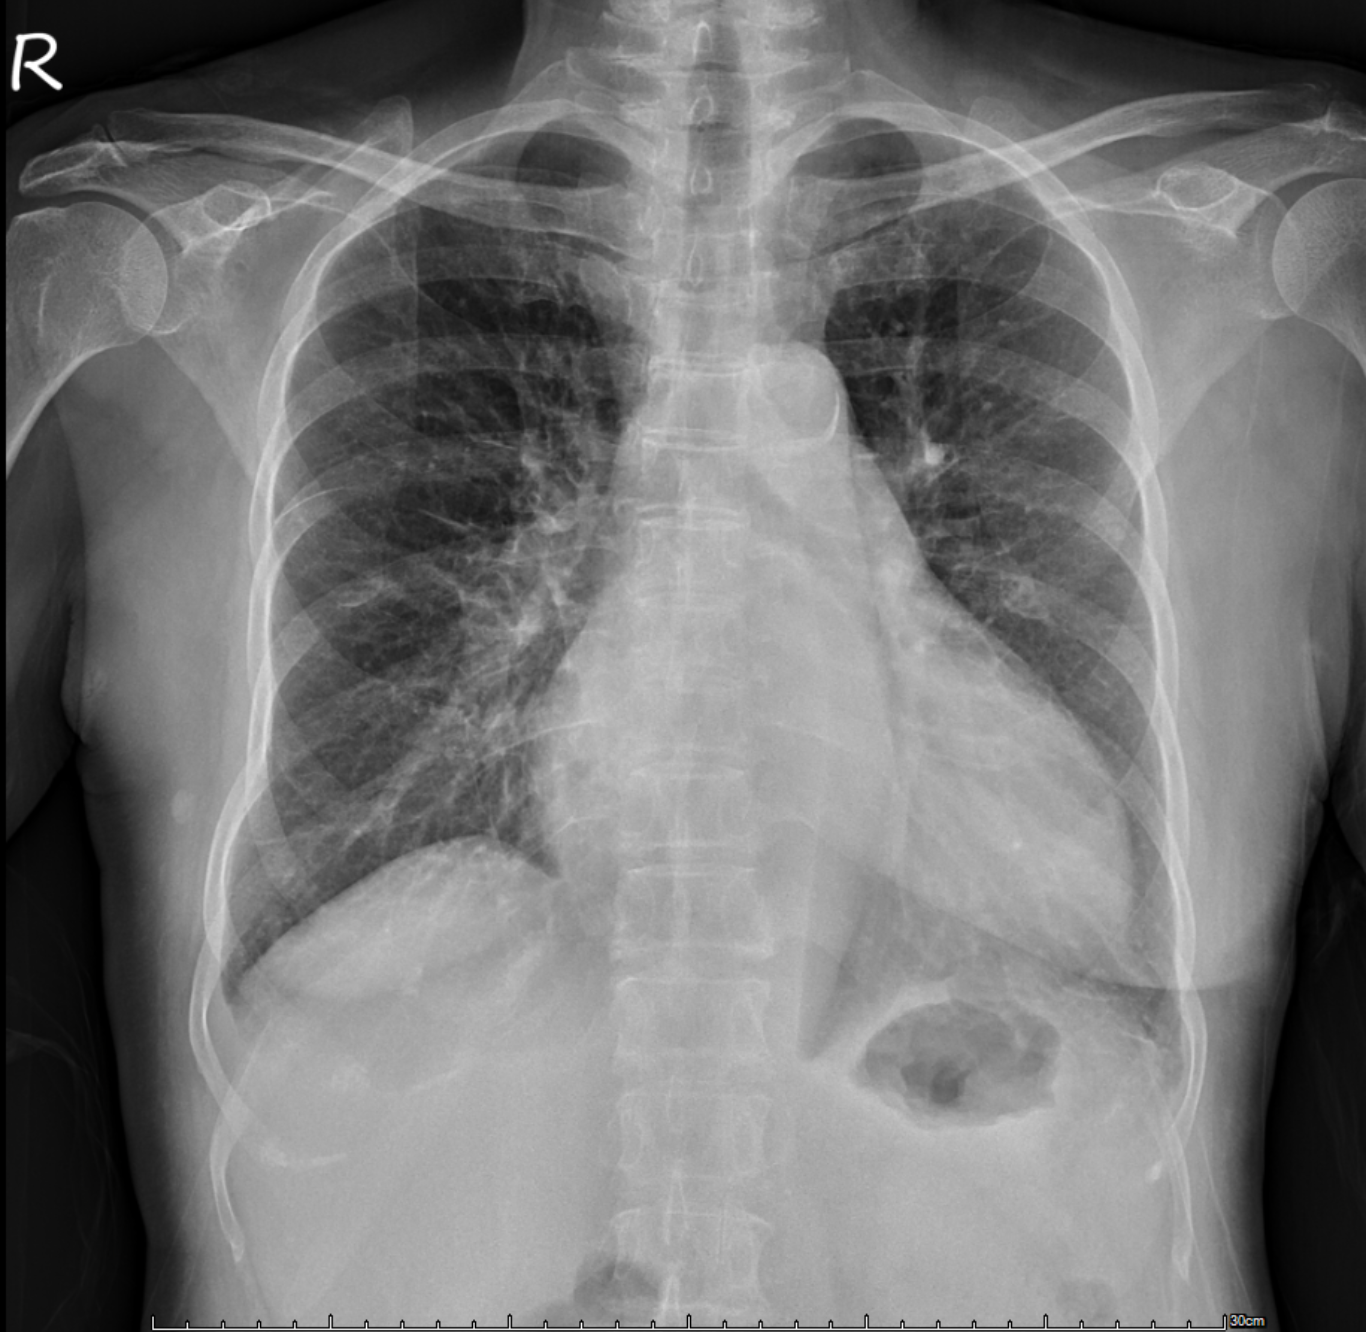

Relevant Test Results Prior to Catheterization

Echocardiography showed severely reduced LV systolic function with an EF around 20%, global hypokinesia, and anterior septal hypokinesia. Severe mitral regurgitation with left atrial enlargement was noted. Mild RV dysfunction was present, and Doppler suggested elevated filling pressures. These findings were obtained prior to catheterization.